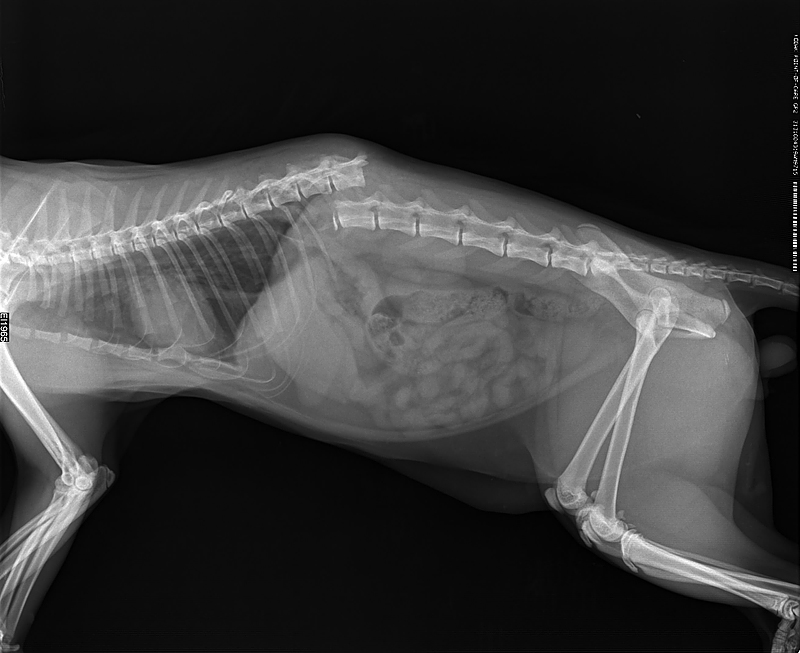

Истончение костей у кошек: причины и решения

Раздел: Мудрость в объективе